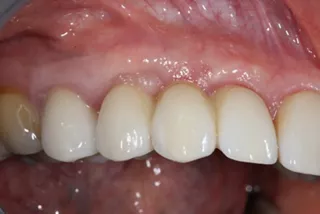

16a-b. Final situation after inserting bridges to 15 Ncm, cementing the crown to tooth 15, and gluing the veneers to teeth 11 and 21.

18. Situation 4 years post implant placement.